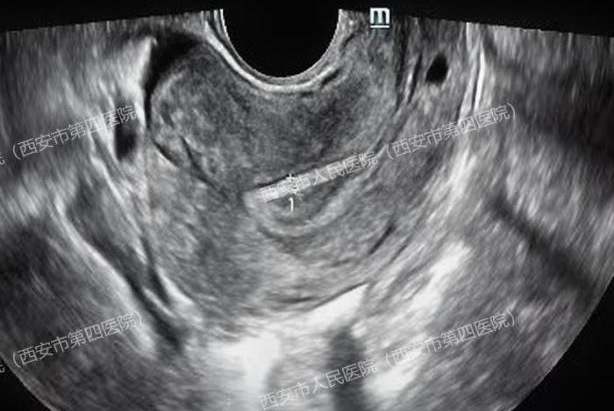

关医生仔细扫查发现:

子宫内未见明显孕囊,右侧卵巢内小囊肿,双侧附件区未看见其他包块。通常,人绒毛膜促性腺激素(HCG)达到1000~2000mIU/ml左右就能看到孕囊,但王女士的HCG水平上升到90000mIU/ml时,超声却没有提示宫内孕囊。理论上来说即使真的宫外孕,包块应该很大、很明显,一眼就能找到才对啊?

医生觉得疑惑,耐心安抚患者的同时又全面细致的沿子宫周围及上方扩展了扫查范围,当扫查到肝脏时,顿时惊呆了......